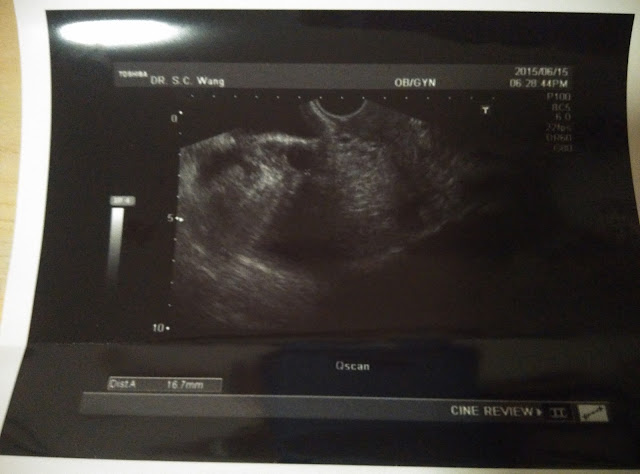

我最大的那個卵泡在右方,直徑為1.67cm。

而左邊最大的卵泡,就只有1.23cm。

其實,如果只計卵泡,用了12天便有1.67,我已經很滿意了。

可惜內膜卻很薄,只有5mm,根本不適宜植入。

她說已大了一點點,約有1.7cm,

但我問她看照片上只有1.65cm,不是比之前還細了嗎。

她解釋因角度的問題,剛剛看到有其他角度是大一點的。

至於內膜就厚了一點點,由5mm增厚至6mm。

醫師見到我卵泡的照片也認為不錯,

但當她知道我剛剛已打了破卵針就有點不滿,

因為她認為卵子及內膜是可以再養的。

但現在內膜還是不夠,我只好向她解釋說西醫認為破卵針會使內膜增厚。